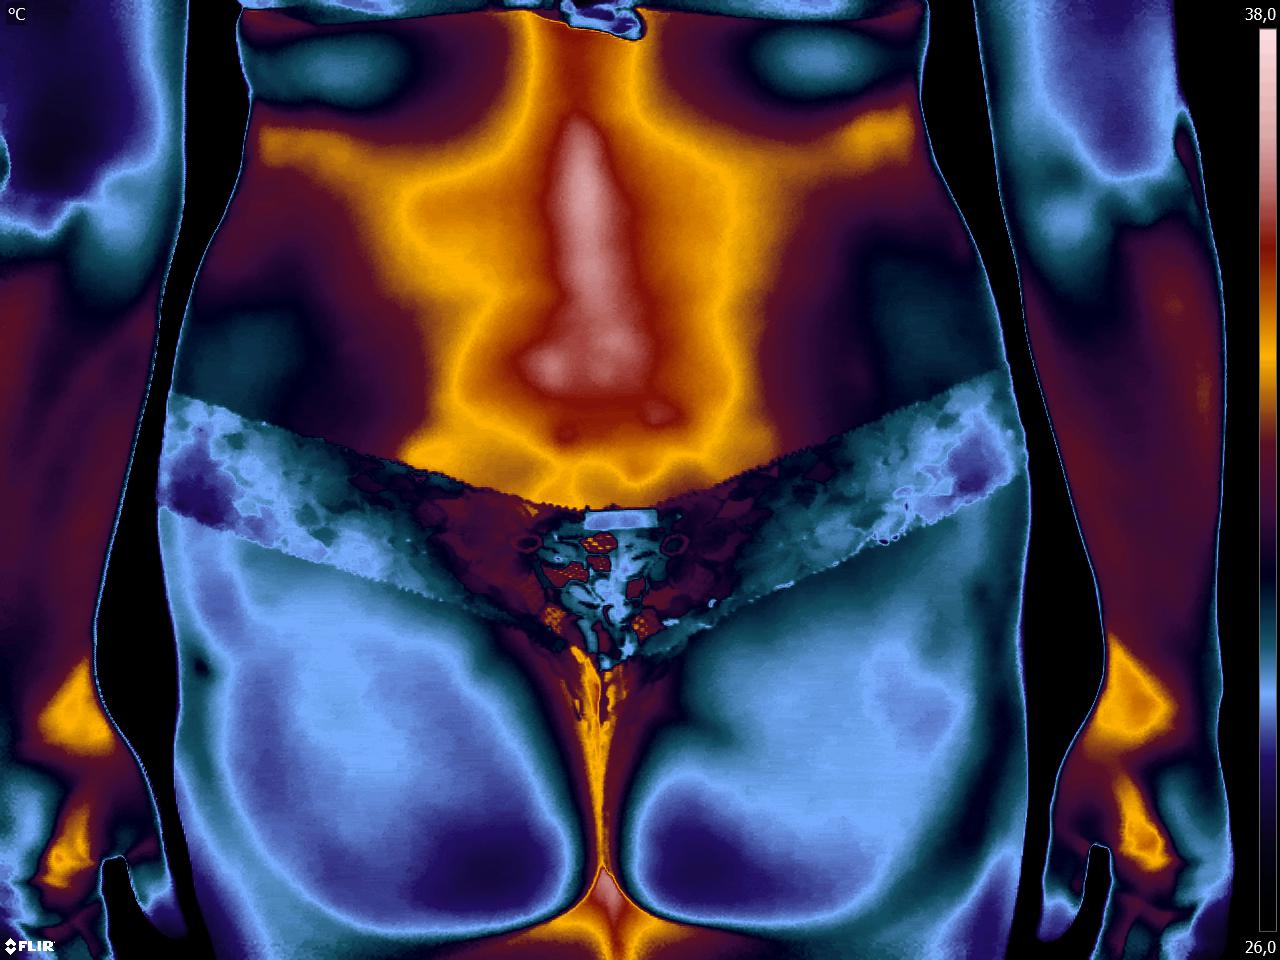

Caros colegas, fisioterapeuta e terapeuta ocupacional, vocês sabiam que com a Termofuncional vocês podem diagnosticar disfunções e até lesões no […]

Caros colegas fisioterapeutas e terapeutas ocupacionais, vocês sabiam que com a Termofuncional vocês podem detectar a disfunção em tempo real? […]